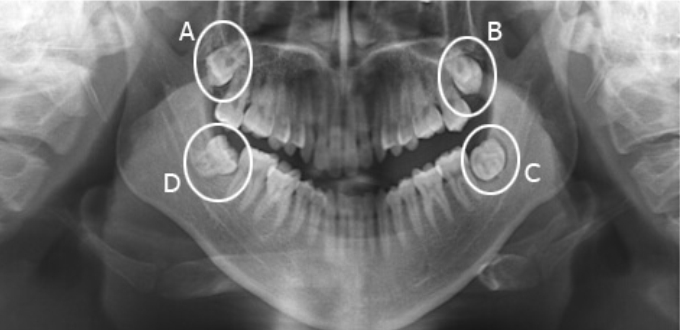

Đến với Nha khoa Dentel, mỗi khách hàng sẽ chụp X-quang cùng máy CT Cone Beam trong quá trình thăm khám tổng quát. Phim X-quang và phim 3D sẽ cho phép bác sĩ có thể thấy rõ được hình dáng, kiểu mọc của răng khôn. Từ đó đưa ra một phương án nhổ sao cho phù hợp mà lại an toàn.

Răng 8 là răng có các kiểu mọc phức tạp. Đặc biệt là phần chân răng. Để có thể chuẩn đoán chính xác cũng như lên phương án nhổ phù hợp, khách hàng sẽ tiền hành chụp phim X-quang, phim 3D với thiết bị công nghệ cao. Nhờ đó có thể thấy rõ hình dáng hoàn chỉnh chiếc răng 8, ngay cả trong trường hợp mọc ngầm bị lợi trùm, mang lại một phác đồ điều trị chuẩn xác – hoàn hảo.

Với phim chụp X-quang, phim chụp cắt lát từ máy CT Cone Beam, cho phép xác định rõ tới từng milimet. Giúp bác sĩ có thể tránh tuyệt đối những khoảng giới hạn không xâm phạm cũng như không gây tổn thương tới mô mềm và vùng răng bên cạnh. Nhờ đó mà bạn có thể yên tâm lựa chọn Nha khoa Dentel để thực hiện loại bỏ răng khôn nhanh chóng – an toàn và hiệu quả.

Phim chụp cắt lát trước khi nhổ răng khôn